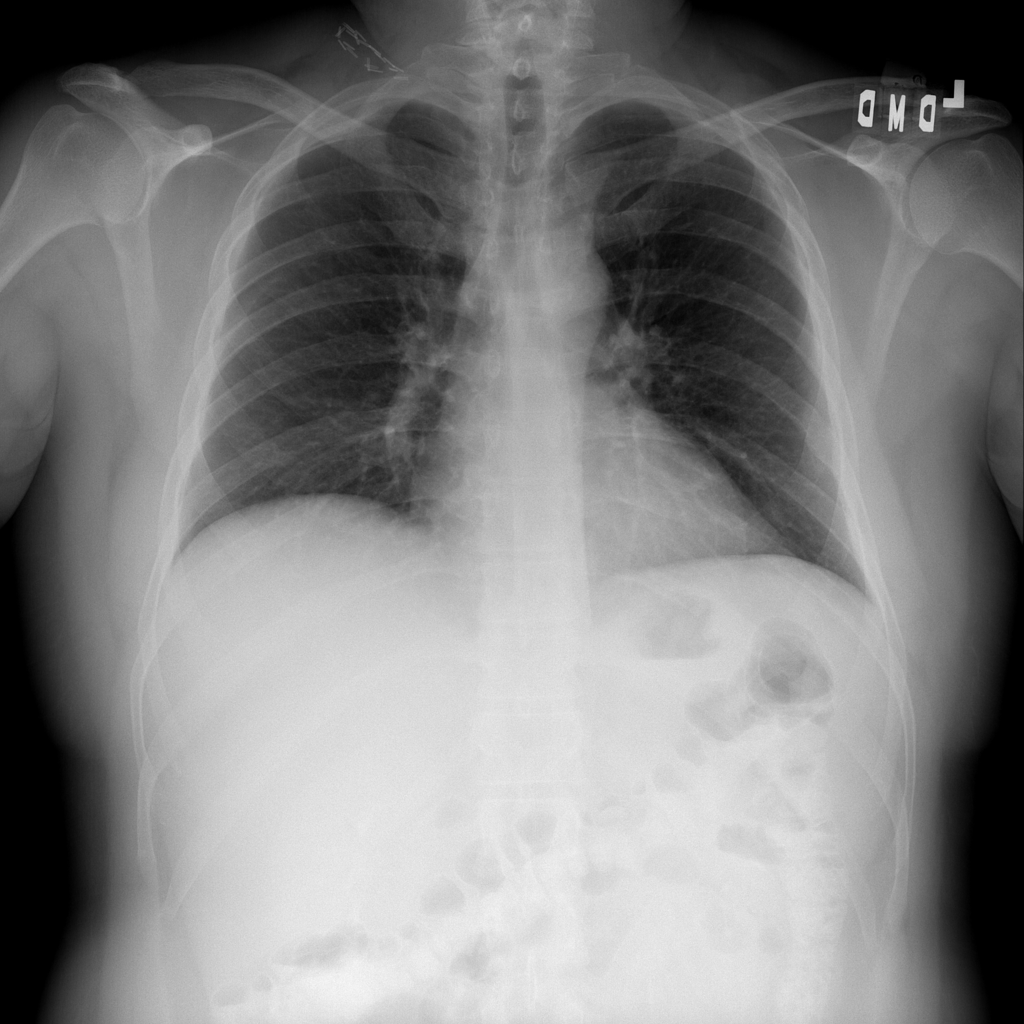

PAT-B3C3 · IMG-001Pneumonia

PAT-B3C3 · IMG-001

PA